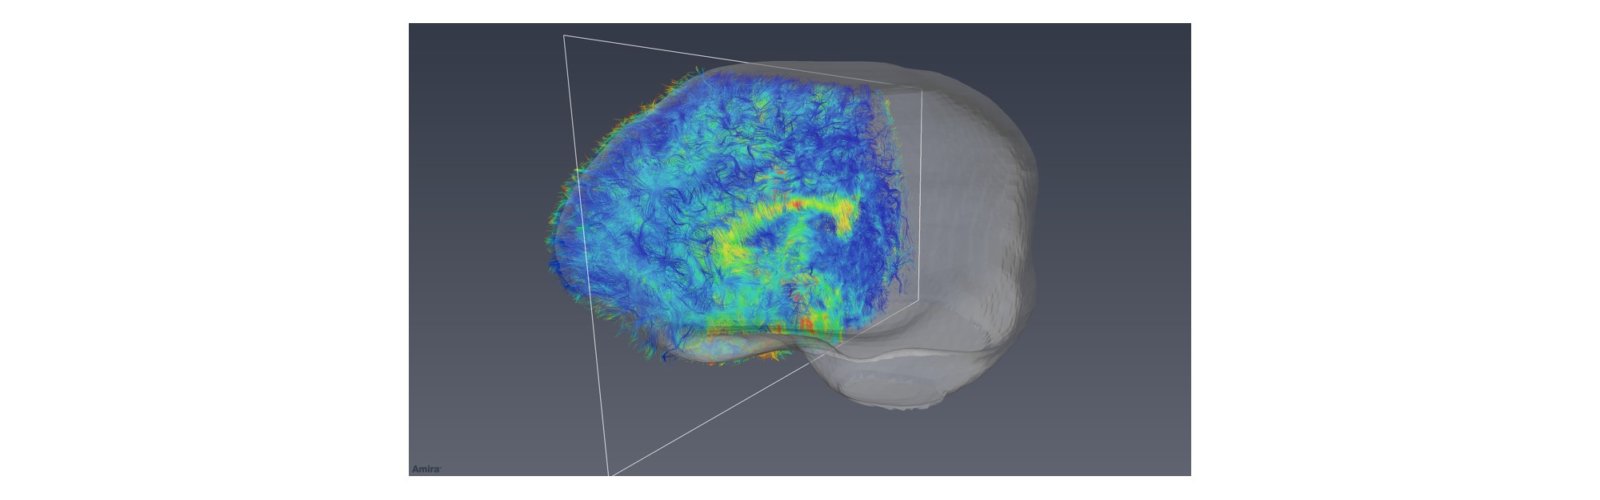

To provide image processing and analysis service to help scientists and clinicians develop imaging biomarkers using different imaging modalities with the goal of:

• Detecting and diagnosing diseases to enable an early stage to enable early treatment intervention.

• Tracking disease progression/tissue regeneration allowing clinicians to evaluate the medical condition.

• Monitoring treatment effects either via conduits for drug delivery and regenerative medicine applications or via other interventional procedures to facilitate therapeutic mechanisms.